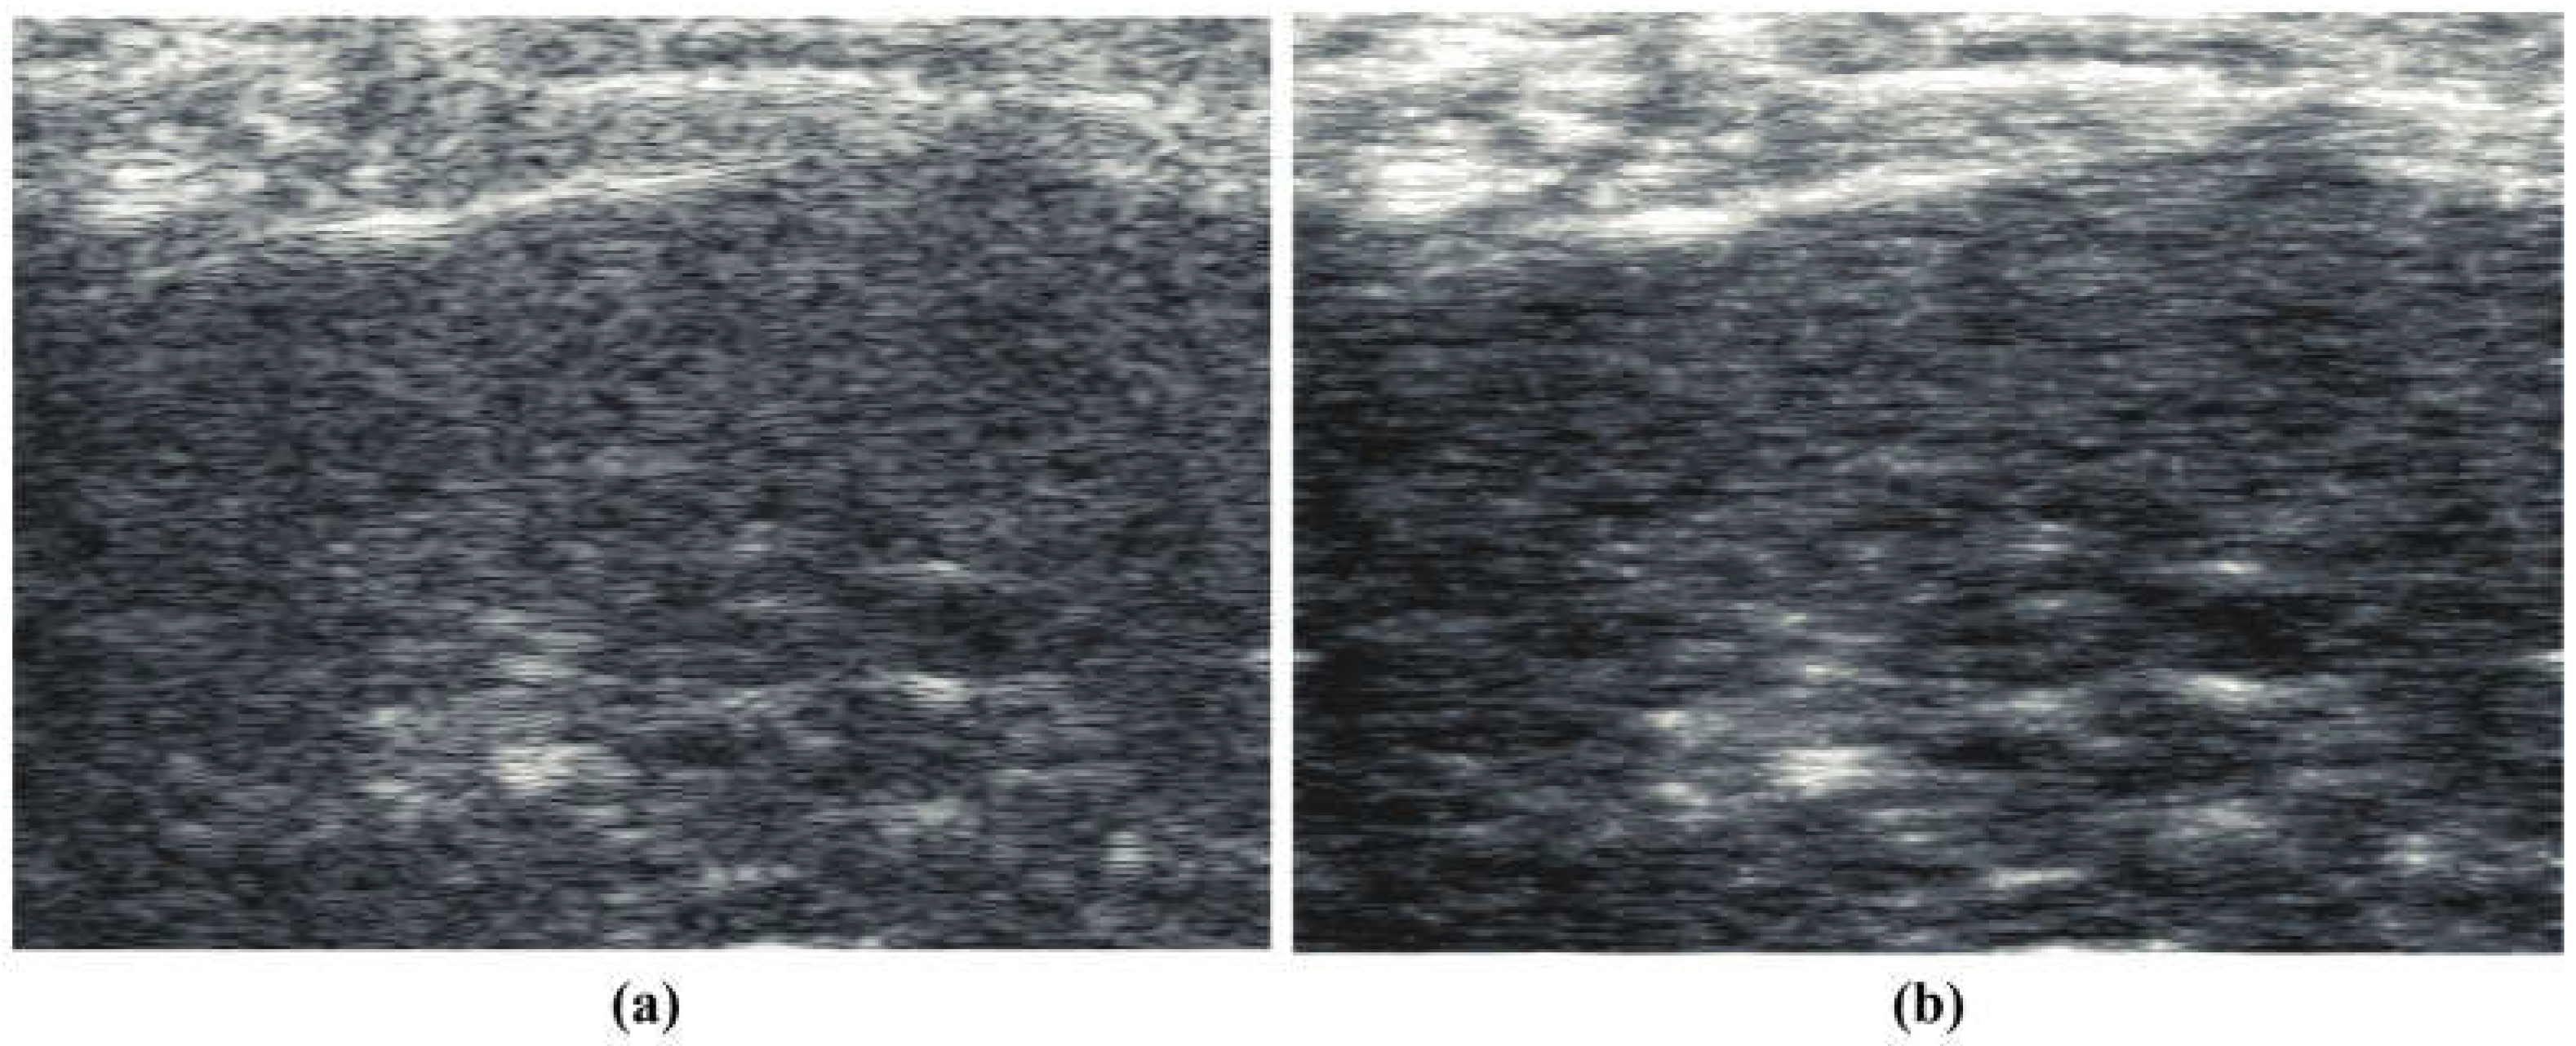

4. Results